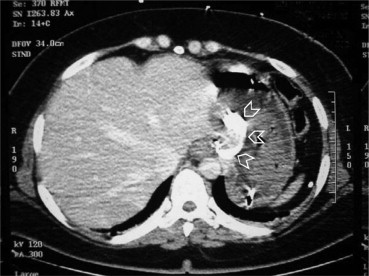

Computed tomographic scan of the abdomen with intravenous contrast showing the ...

Figure 1.

Computed tomographic scan of the abdomen with intravenous contrast showing the gastric band (arrowheads) eroding through the stomach wall. No free air or fluid in the peritoneum was detected.

Upper gastrointestinal endoscopy showed an eroding gastric band protruding into the proximal stomach and fresh blood clot without active bleeding. The patient became hemodynamically stable, and the urine output improved to 100 mL/h. Computed tomographic scan of the abdomen with intravenous contrast showed migration of the gastric band into the stomach. There was no intraperitoneal fluid or free gas (Fig. 1). The patient stayed in the intensive care unit for 2 days and was transferred to the surgical ward where she was managed conservatively and did not require surgery. The patient was discharged to be followed up at the Morbid Obesity Unit at Tawam Hospital. She was advised to wait until the erosion is complete so as to remove the band endoscopically.